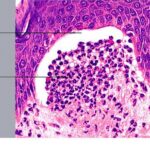

. The typical histologic features are best observed in erythematous skin adjacent to early blisters. In these zones, neutrophils accumulate at the tips of dermal papillae. With an increase in size to microabscesses, a significant admixture of eosinophils may be noted. As microabscesses form, a separation develops between the tips of the dermal papillae and the overlying epidermis; thus, the early blisters are multiloculated . The presence of fibrin in the papillae may give them a bluish appearance. Within 1 to 2 days, the rete ridges lose their attachment to the dermis, and the blisters then become unilocular  and clinically apparent. At this time, the characteristic papillary microabscesses may be observed at the blister periphery. For this reason, the inclusion of perivesicular skin in the biopsy specimen is of

utmost value. The papillary dermis beneath the papillae may have a relatively intense inflammatory infiltrate of neutrophils and some eosinophils. Many neutrophils may exhibit leukocytoclasis. Subjacent to this, a perivascular infiltrate composed of lymphocytes, neutrophils, and eosinophils may be apparent. the diagnostic finding of papillary microabscesses may not be present in all patients. Apoptotic keratinocytes may be noted above the papillary microabscesses.